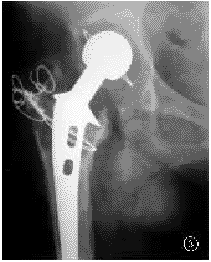

图4髋臼Delee一、二、三区及股骨Gruen一、七区膨胀性骨溶解(箭头所示);股骨Gruen一、二、六、七区衬性骨溶解(左侧);左侧髋臼假体移位,双侧股骨柄假体下沉